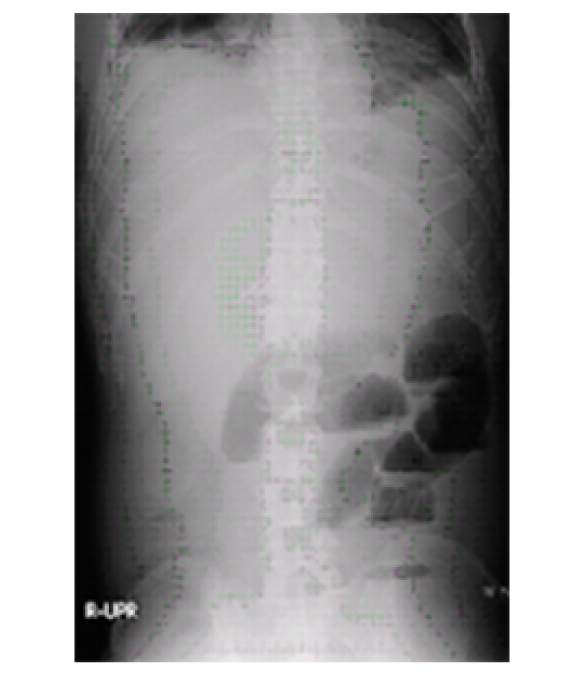

単純X線撮影